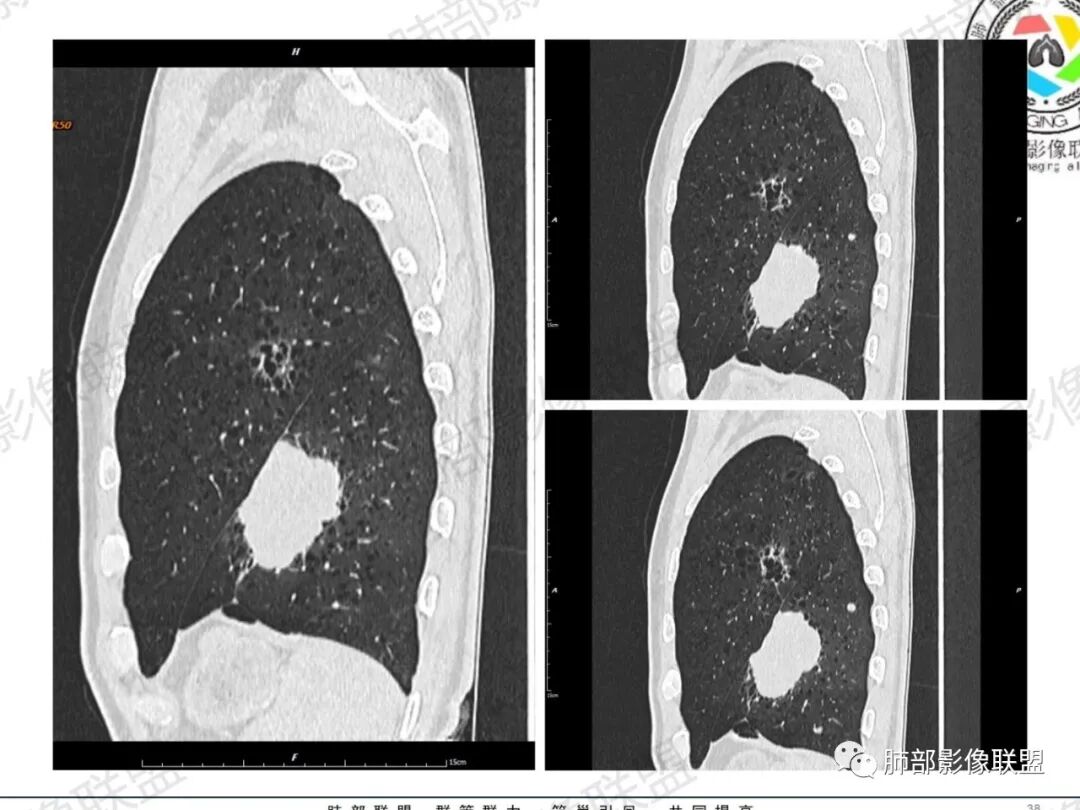

一切∮随缘:左肺下叶不规则肿块,边缘光滑,平直,局部彭隆,分叶,近端支气管堵塞,远端与胸膜相贴,平扫密度尚均匀,增强后不均匀强化,内部可见低密度坏死,胸膜下多发肺气肿,伴双肺散在光滑小结节,实验室肿瘤标志物高,考虑恶性:神经内分泌癌(大细胞),腺癌,鳞癌。

琦遇:恶性没有问题,肺气肿底子、病灶分叶、少许毛刺、叶间胸膜凹陷、部分边缘可见清晰的GGO、胸膜牵拉凹陷、局部胸水、近端支气管截断、部分支气管被推移、占位效应明显、强化特点为不均匀强化、内部有少许沼泽样低强化区,强化部分轻中强化为主、余肺可见转移性结节、左肺上叶似为囊腔型腺癌一枚,肿瘤标志物提示非小、神经内分泌,综合分析考虑大神泌、腺癌、腺鳞癌、鳞癌  同时左肺上叶囊腔型腺癌  肺转移

飞鹰行动:中年人,男性,胸疼入院,左肺下叶占位,张力较高,边界可见分叶,局部可见明显收缩性改变,增强病灶内部有延迟强化表现,考虑恶性病变,大细胞癌伴肺内转移或者囊腔样腺癌伴转移。

蕊:中老年男性,吸烟史,肺气肿背景,左肺上叶类圆形肿块影,边界清晰,边缘凹凸不平,有分叶,支气管进入阻断,临近胸膜栽赃,整体病灶膨隆,局部周围可以清晰ggo,临近叶间裂内凹,轻度强化,并可见多个低密度区,坏死可能,界线不清;肺内多结节,边缘光滑,考虑恶性伴转移,鳞癌、腺癌

傅昌瑜:中老年男性,肺气肿背景,右胸背疼痛1周。CEA、NSE、CYFRA—211升高。左上肺混合磨玻璃结节,内见较多空泡和扩张支气管。左下肺胸膜下肿块,边缘较光滑,深分叶,似有血管进入,与支气管关系不清,内见不均匀强化,见沼泽地样坏死,有胸膜栽赃。另两肺多发圆形小结节。考虑恶性并肺内转移,多原发可能性大,左上肺腺癌,左下肺病理难以判断,小细胞癌?鳞癌?

小锁:中老年男性,肺气肿背景,右胸背疼痛1周。CEA、NSE、CYFRA—211升高。左上肺混合磨玻璃结节,边界清楚,内见较多空泡。左下肺肿块,边缘清楚,深分叶,有血管和支气管进入,胸膜凹陷。另两肺多发圆形小结节。考虑双发原位癌,左上肺腺癌,左下肺大神泌或腺鳞癌可能,肺内转移。

蓝天白云:中年男性,肺气肿背景,左肺下叶肿块,边缘膨隆,有分叶,内有湖泊样坏死,有轻中度强化,局部胸膜栽赃,收缩力不强,周围见肺气肿征象。左肺上叶混合磨玻璃影,边界清楚,考虑都是恶性,左上肺iac,左下肺腺鳞癌,或大细胞肺癌可能。两肺多发结节,考虑转移

毛勤香:老年男性,肺气肿背景,左肺下叶肿块,分叶,边缘光滑,土豆块样,细支气管闭塞,增强轻度不均匀强化,似有坏死,左肺另见多发结节,淋巴结未见明显肿大,恶性确定,吸烟史,鳞癌破坏力强,侵袭力差,多原发的一般很少多于3个,故排后,首先考虑神经内分泌癌,局部血管穿行,鉴别淋巴瘤

周太狼:中年男性,吸烟、高血压史,肿瘤指标升高,肺气肿背景下,左肺下叶肿块影,分叶、膨隆、未跨叶裂,支气管截断,不均匀强化。另双肺多发结节及磨玻璃影,左肺上叶混合磨玻璃,内可见多发空泡影。整体考虑恶性,肺癌伴肺内转移,左下肺鳞癌?神经内分泌癌?左肺上叶囊腔腺癌?